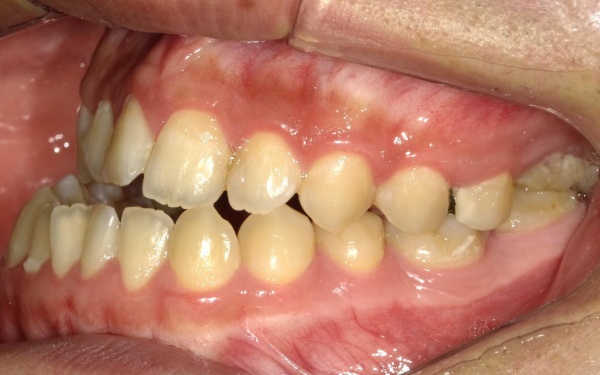

治療前

治療前画像

カウンセリング・診断結果 拝見したところ、骨格の問題により下前歯が上前歯より前に出ている前歯部反対咬合と、前歯が開いて噛み合わないオープンバイトが認められました。

さらに、下顎の骨が右方向にずれて上下の歯が噛み合う面が斜めになっていることで、顔面の非対称も見られます。

これらは顎変形症と呼ばれる状態で、現在は食べ物をしっかりと噛む機能が大きく制限されているうえ、発音や見た目に悪影響が出ていました。

治療前画像 治療前画像 治療前画像 治療前画像 治療前画像 治療前画像